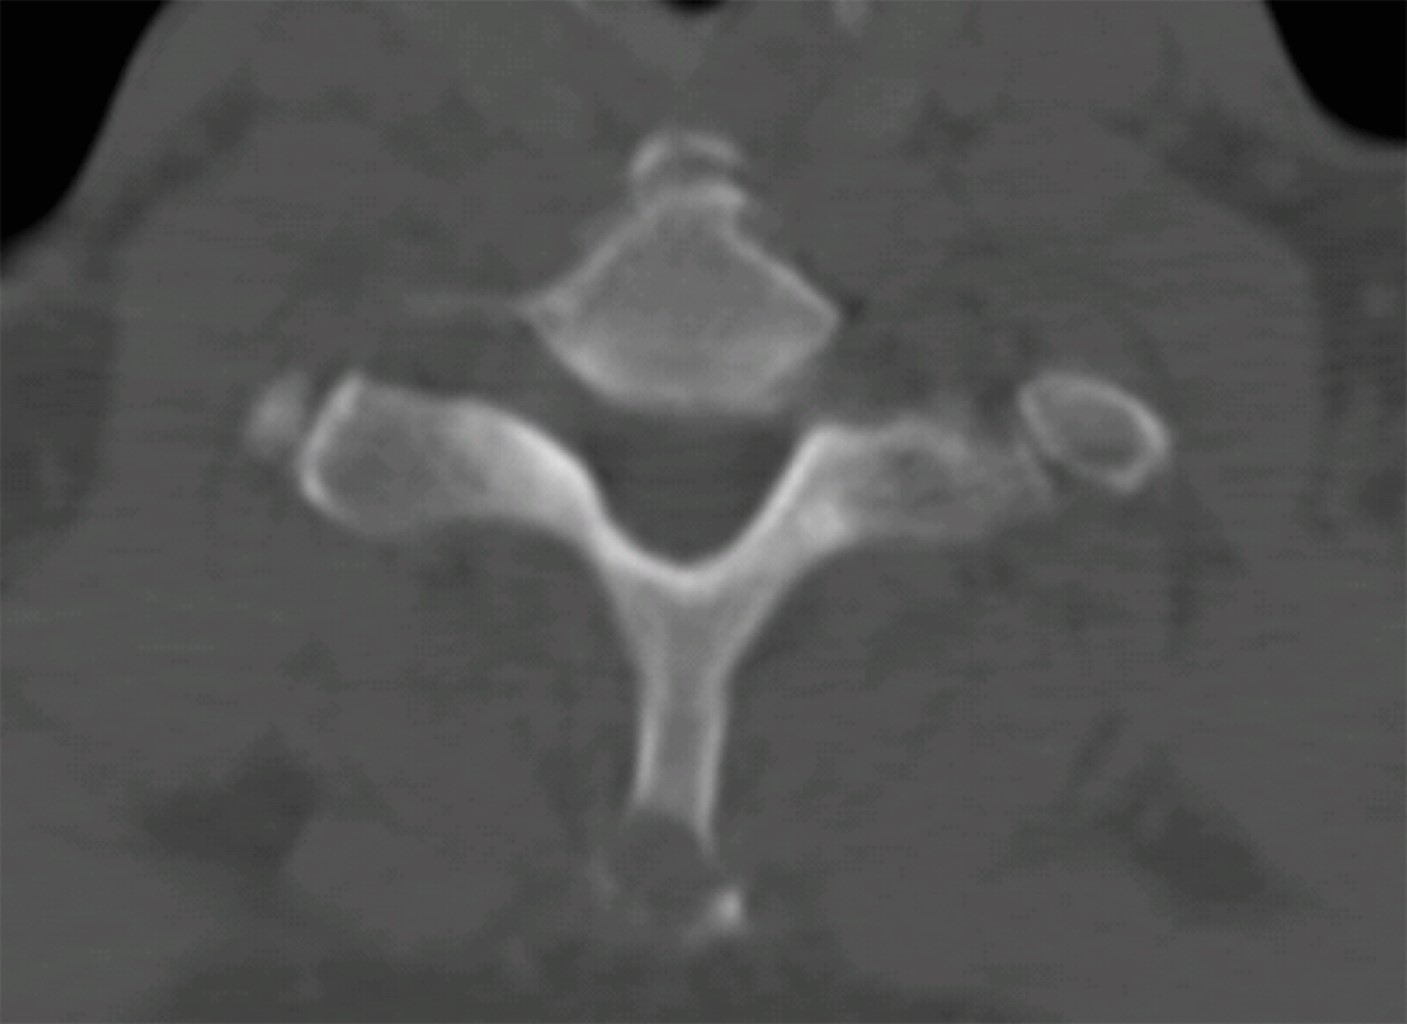

El paciente aporta una tomografía axial computarizada (TAC) y una resonancia magnética nuclear (RMN) (Figuras 1 y 2) que muestran una lesión lítica inespecífica en la espinosa de T1 y otra lesión en el cuerpo vertebral de L2. Ante estos hallazgos, se solicita una gammagrafía y una TAC toracoabdominal y se reprograma al paciente en una semana en consultas. Se realiza la gammagrafía que sólo muestra captación a nivel de ambas lesiones vertebrales. La TAC toracoabdominal informa de un enfisema paraseptal con atelectasias en el lóbulo inferior derecho y un área inespecífica en vidrio deslustrado en el lóbulo medio, sin alteraciones en el parénquima pulmonar ni otras lesiones a nivel abdominal.

Figura 1